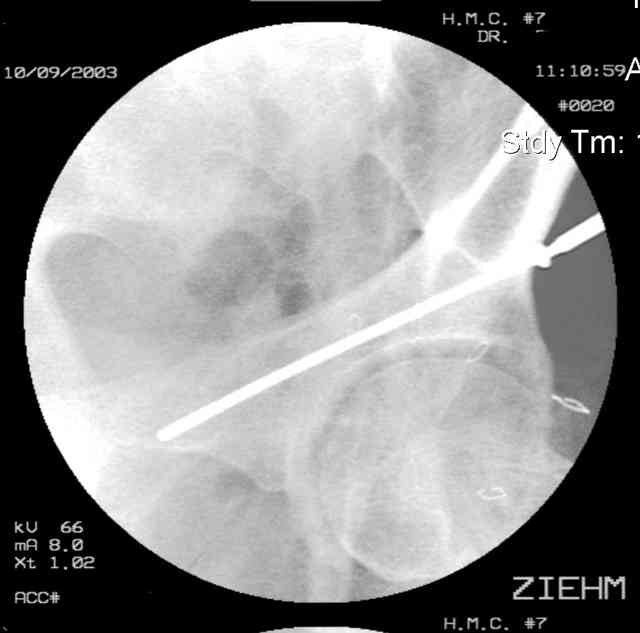

I'll include a few images of a similar injury in a similarly large male patient. This patient "showed up" in our ER c/o hip pain 2 months after being treated in the lateral position, without a quality reduction, without an anterior column transverse supporting implant, with an unbalanced plate applied too medially, with insufficient caudal segment fixation...it took over 8 hours and a 3+ l blood loss to debride the callus from front then

back, excise the HO, release his sciatic nerve, reduce the head-transverse-wall, and fix it...and now it's a staging procedure.

The 2nd example is of a motorcyclist with a transverse fracture-dislocation...he had a closed attempted reduction and placed in traction but the manipulative reduction was not concentric (not unusual for this injury pattern)...so the traction was adjusted to be just enough to disengage the head from the fracture (12#) until he could be cleared for surgery one day after injury...he was treated "urgently" then with a prone KL, clean the fracture, reduce and clamp it, screw it, support with a balanced plate, close, and enjoy...2-3hours, 400cc EBL, blah, blah, blah..